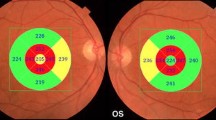

However, as described below, the reduction in RNFL thickness observed in most studies on AD patients was significantly greater than that observed in the age-matched controls and thus cannot be exclusively ascribed to aging (see some illustrative OCT imaging in Fig. 13.1 and a synopsis of published OCT studies in AD and MCI in Table 13.1).

Optical Coherence Tomography (OCT) imaging taken in cylindrical section of tissue surrounding the optic disc of a control eye and of 2 AD patients eyes. The images in the left panel are raw OCT data, while the maps in the right panel are quantitative data curve. In AD patients eyes OCT shows a decrease of RNFL reflection (reduced RNFL thickness) in each examined quadrant, with particular prevalence of the temporal ones